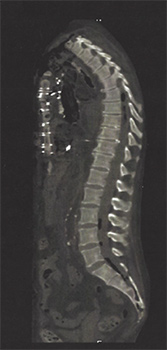

Scoliosis correction

Spine surgery that involves the removal of bone to help restore flexibility to the spine and allow for correction of the curve, placement of specialized implantable screws, and spinal fusion*